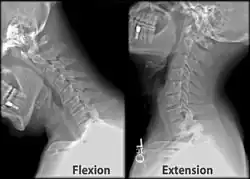

Skull and cervical vertebra. Position of condyloid fossa shown in red. | |

Skull and cervical vertebra. Position of condyloid fossa shown in red.

Skull and cervical vertebra. Position of condyloid fossa shown in red. -

X-ray of cervical spine (neck) in flexion and extension (bending backwards)

X-ray of cervical spine (neck) in flexion and extension (bending backwards)